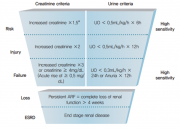

| 2019년 5월 28일 (화) 01:34 | 비뇨기계장애감정지침서 그림2.png (파일) |  |

171 KB | Sjlee | 1 | |